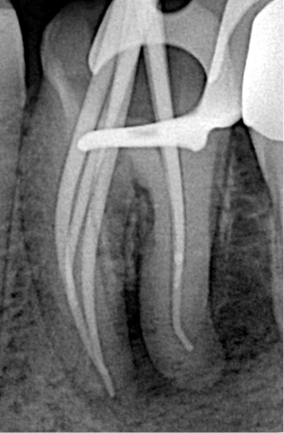

Working length (WL) was precisely determined using the ROGIN Apex_S apex locator. Electronic apex locators provide reliable readings even in wet or infected canals, offering greater accuracy than radiographic methods alone.

Step 4: Canal Shaping

Canal shaping was performed with the ROGIN Elite_Ino endo motor (a cordless brushless motor with integrated apex locator functionality). Due to the severe apical curvature, highly flexible instruments were essential to maintain the original canal anatomy and prevent iatrogenic errors.

Dr. Alani selected ROGIN Super Flexi Files — heat-treated NiTi rotary files known for their exceptional flexibility, high cutting efficiency, and resistance to cyclic fatigue. These files performed excellently in the curved and complex anatomies typical of mandibular molars, allowing safe navigation of the apical third without transportation or ledging.